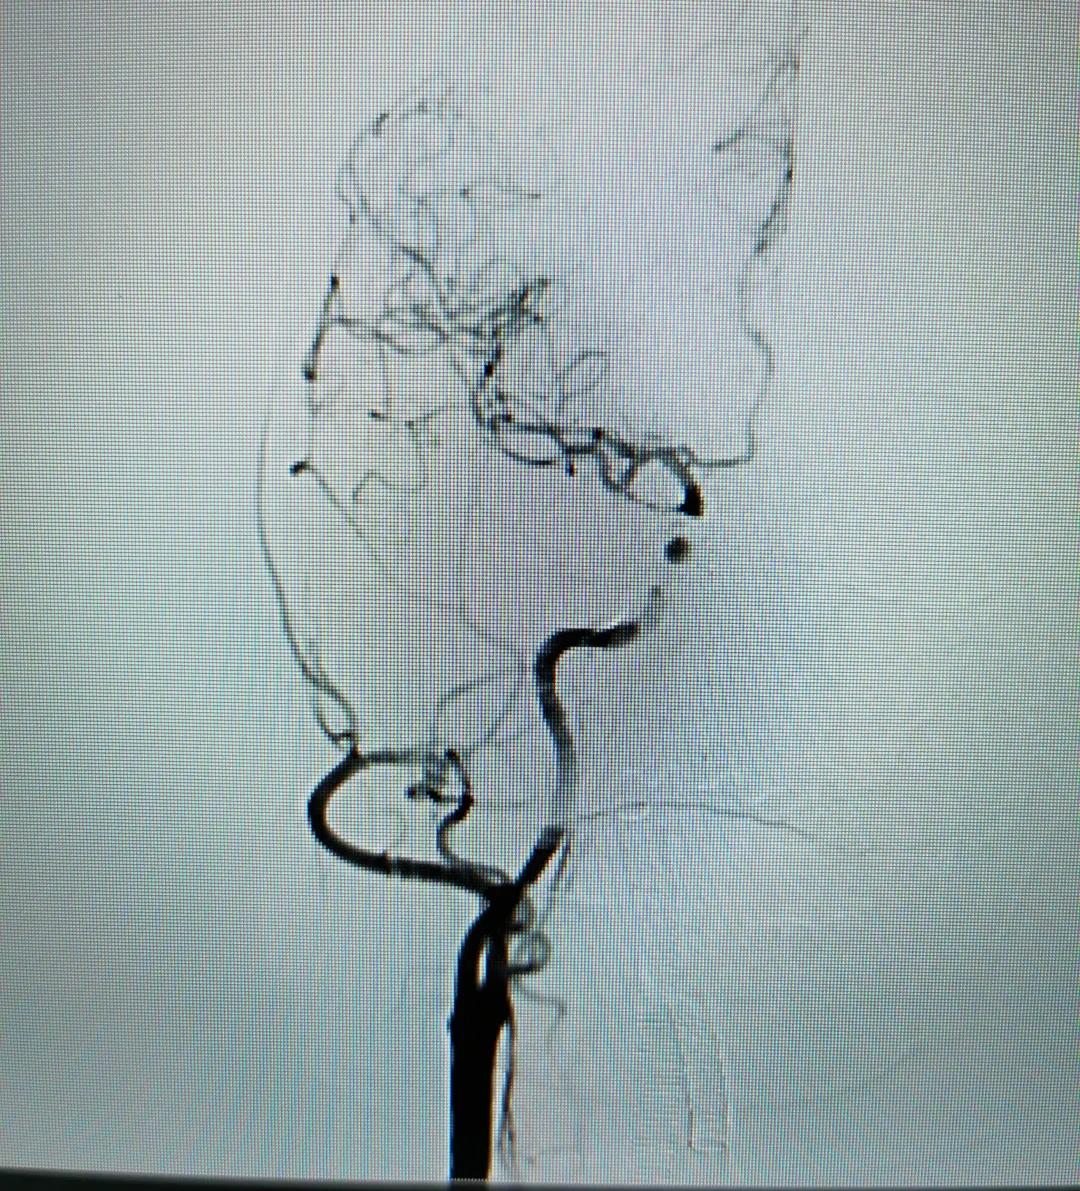

患者术后脑血管造影

成功从岩下窦进入海绵窦是栓塞能否成功的关键,也是考验医生耐心和技巧的最关键步骤。栓塞时更应小心谨慎,因为栓塞剂可能通过瘘口或者危险吻合逸入颈内动脉或眼动脉,这就要求术者必须熟悉血管的解剖,同时术中要眼观六路,仔细观察。经过医护团队紧张有序的治疗,手术成功。

术后,张女士的瘘口完全闭塞,颅内血流恢复正常,“眼疾”也恢复了。经过医护团队的精心治疗与护理,患者顺利出院。